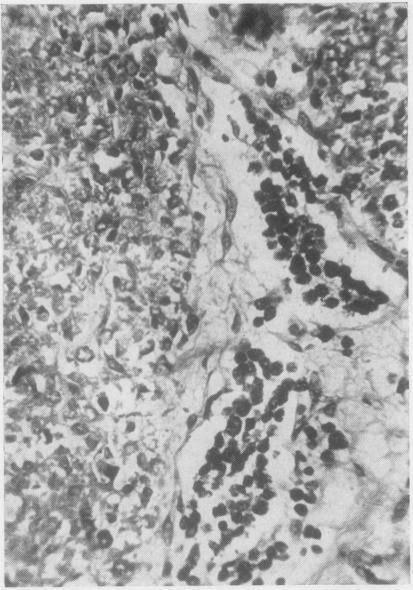

先天性神经母细胞瘤

CONGENITAL NEUROBLASTOMA.

Abstract

The clinical histories and post-mortem findings in five cases of neuroblastoma are described, and an account given of the microscopic characteristics of the tumours. In four of the cases the tumour was present at birth and was probably so in the fifth case. In only one case was the presence of the malignant tumour a significant factor in causing death. The differential diagnosis of such tumours is discussed.The accumulated evidence of many recorded cases suggests that neuroblastoma, becoming manifest in the early months or weeks of life, and congenital tumour, would be included in such a group, and has an appreciably better prognosis than has this same tumour when it becomes manifest in later childhood. The literature is briefly reviewed to illustrate this aspect of prognosis and possible reasons for it are indicated.

摘要

本文描述了5例神经母细胞瘤的临床病史和尸检结果,并阐述了肿瘤的微观特征。其中4例肿瘤在出生时就已存在,第5例可能也是如此。只有1例中,恶性肿瘤的存在是导致死亡的重要因素。文中讨论了此类肿瘤的鉴别诊断。许多已记录病例的累积证据表明,在生命最初几个月或几周内出现症状的神经母细胞瘤以及先天性肿瘤,应归为同一组,其预后明显优于在儿童后期出现症状的同类型肿瘤。本文简要回顾了相关文献以说明预后的这一方面,并指出了可能的原因。